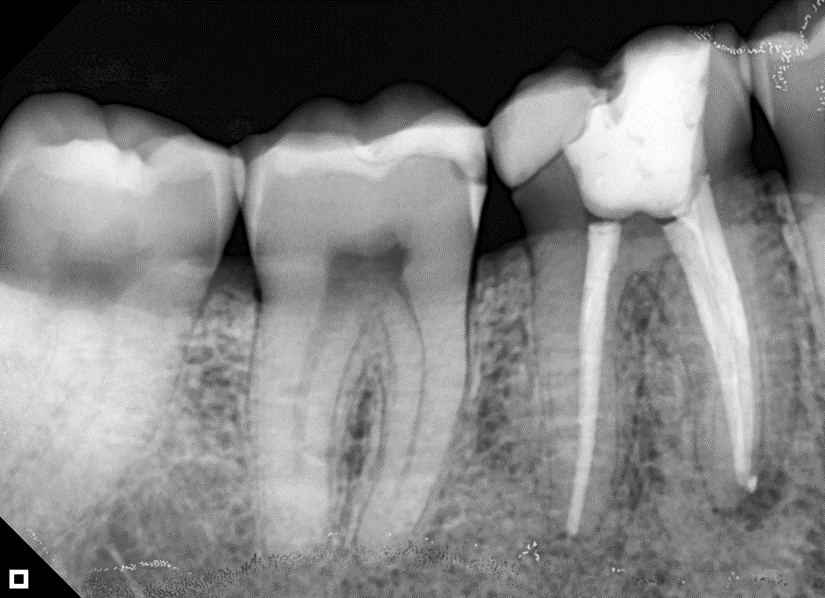

O paciente apresentou fratura vertical mésio-distal no elemento 46. Foi planejada a exodontia minimamente traumática e instalação imediata do implante Maestro Superiore (Implacil Osstem) utilizando uma guia prototipada. Após a exodontia, o implante foi instalado seguindo o protocolo de cirurgia guiada. O GAP vestibular foi preenchido com o Extra Graft. Um cicatrizador personalizado impresso com haletas facilitadoras foi capturado com resina flow e instalado. Após 30 dias, foi realizado escaneamento indireto para obtenção do perfil de emergência, utilizando protocolo digital com sobreposição do cicatrizador escaneado para confecção da coroa definitiva em zircônia policristalina estabilizada por ítria.

A reabilitação imediata de áreas posteriores com implantes instalados no alvéolo pós-extração tem mostrado alta previsibilidade, especialmente quando associada a guias cirúrgicos prototipados e componentes personalizados. O uso de implantes com conexão cônica interna, como o Maestro Superiore (Implacil Osstem), proporciona maior estabilidade mecânica e melhor vedação bacteriana na interface implante/pilar, contribuindo para a manutenção óssea marginal1,2.